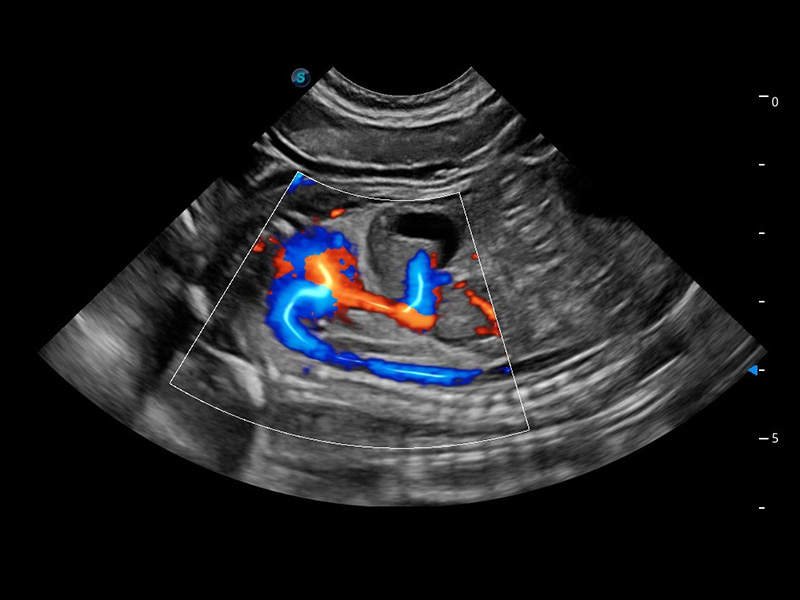

ProPet 60 作为一款高端台式动物超声设备,为动物医生的日常诊断提供了一系列贴合动物临床需求、解决临床实际问题的高级成像功能。凭借全系列高清探头,满足医生对腹部、心脏、生殖、浅表、肌骨等成像的所有需求,切实帮助您提升检查效率,提高诊断信心。

动物是人类最亲密的朋友和最值得信赖的伙伴。环球UG官网也一直致力于探索动物专用的超声影像解决方案。 全新推出的ProPet系列,是环球UG官网在动物超声影像智能化、专业化、精准化的一次跨越式革新。动物不能用言语来表述自己的不适,通过超声影像,ProPet系列搭建了动物医生与不同物种沟通的“桥梁”,为动物医生注入了“治愈之力”。